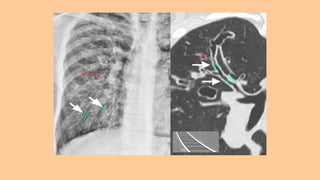

a. Plain Chest X-ray -

Tram-track opacities i-e. dilated bronchi with thickened walls (tram-

track sign) or as ring-like markings. Scattered Irregular Opacities ,

Atelectasis & Focal consolidation may be present. Overall there appears

to be an increase in bronchovascular markings.

b. HRCT Chest ( Most Sensitive & Specific Test For Diagnosing

Bronchiectasis ) -

• Tram-Track Appearance : Lack of narrowing in the caliber of bronchus

towards periphery i-e. dilated bronchi with thickened walls

• Signet Ring Sign : Bronchus & Pul. Artery should be of same size but in

BE Bronchus is markedly dilated than Pul. Artery

DIAGNOSIS : 1. History+ Physical Examination - Compatible History Of Chronic Respiratory Symptoms i-e. Daily Cough & Purulent Sputum Production 2. Sputum Analysis - Bacteriological & Mycological Ex. Of Sputum 3. Radiological Examinations a. Plain Chest X-ray - Tram-track opacities i-e. dilated bronchi with thickened walls (tram- track sign) or as ring-like markings. Scattered Irregular Opacities , Atelectasis & Focal consolidation may be present. Overall there appears to be an increase in bronchovascular markings. b. HRCT Chest ( Most Sensitive & Specific Test For Diagnosing Bronchiectasis ) - • Tram-Track Appearance : Lack of narrowing in the caliber of bronchus towards periphery i-e. dilated bronchi with thickened walls • Signet Ring Sign : Bronchus & Pul. Artery should be of same size but in BE Bronchus is markedly dilated than Pul. Artery